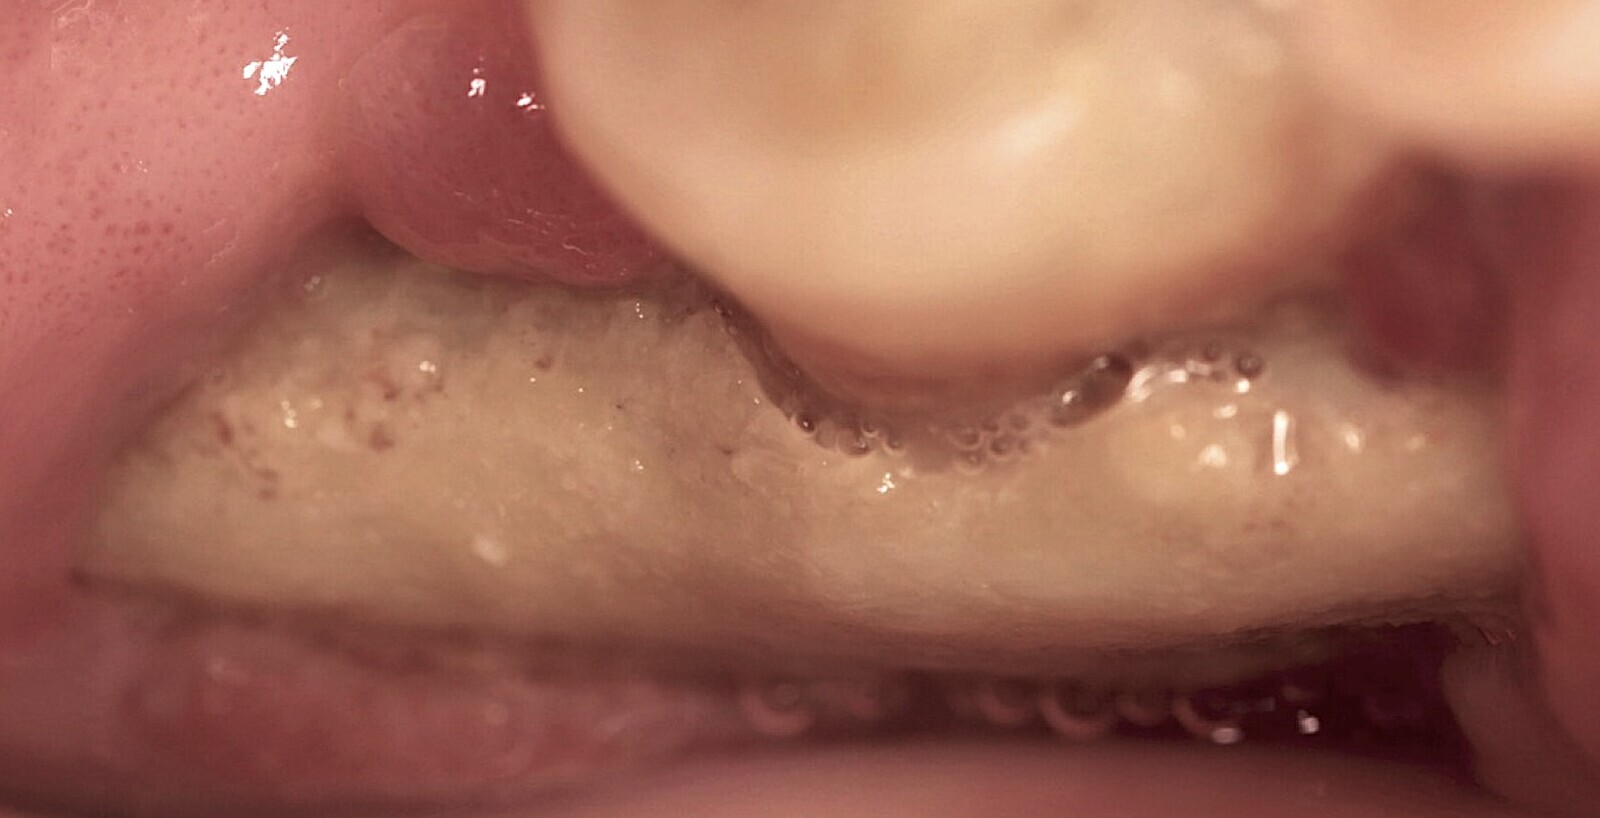

Figura 1. Osteonecrosis maxilar resultado de un tratamiento con un antiangiogénico (anticuerpo monoclonal).

La osteonecrosis de los maxilares relacionada con medicamentos MRONJ (por sus siglas en inglés) se caracteriza por la presencia de hueso expuesto o que puede ser sondado a través de una fístula intraoral o extraoral en la región maxilofacial, que persiste durante más de 8 semanas. Esta condición se observa en pacientes que han recibido tratamiento actual o previo con terapias antirresortivas, solas o combinadas con moduladores inmunológicos, o medicamentos antiangiogénicos, y que no tienen antecedentes de radioterapia o enfermedad metastásica en las mandíbulas[1].

Osteonecrosis maxilar resultado de un tratamiento con un antiangiogénico (anticuerpo monoclonal).